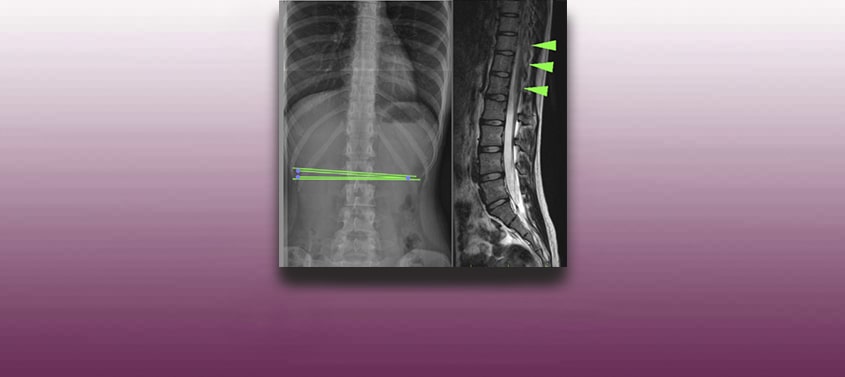

Thorakaler Bandscheibenvorfall

Letzte Überarbeitung: 09/10/2018, Dr. med. Miguel B. Royo Salvador, Arztnummer: 10389. Neurochirurg und Neurologe. Trotz der scheinbaren Ähnlichkeit zwischen einem lumbalen und einem thorakalen Bandscheibenvorfall, verhält es sich bei letzterem in Wirklichkeit etwas anders. Laut einschlägiger Bibliographie, besteht bei dem chirurgischen Eingriff eines thorakalen Bandscheibenvorfalls eine 50%ige Wahrscheinlichkeit, dass das Rückenmark in Mitleidenschaft gezogen wird. Es handelt […]